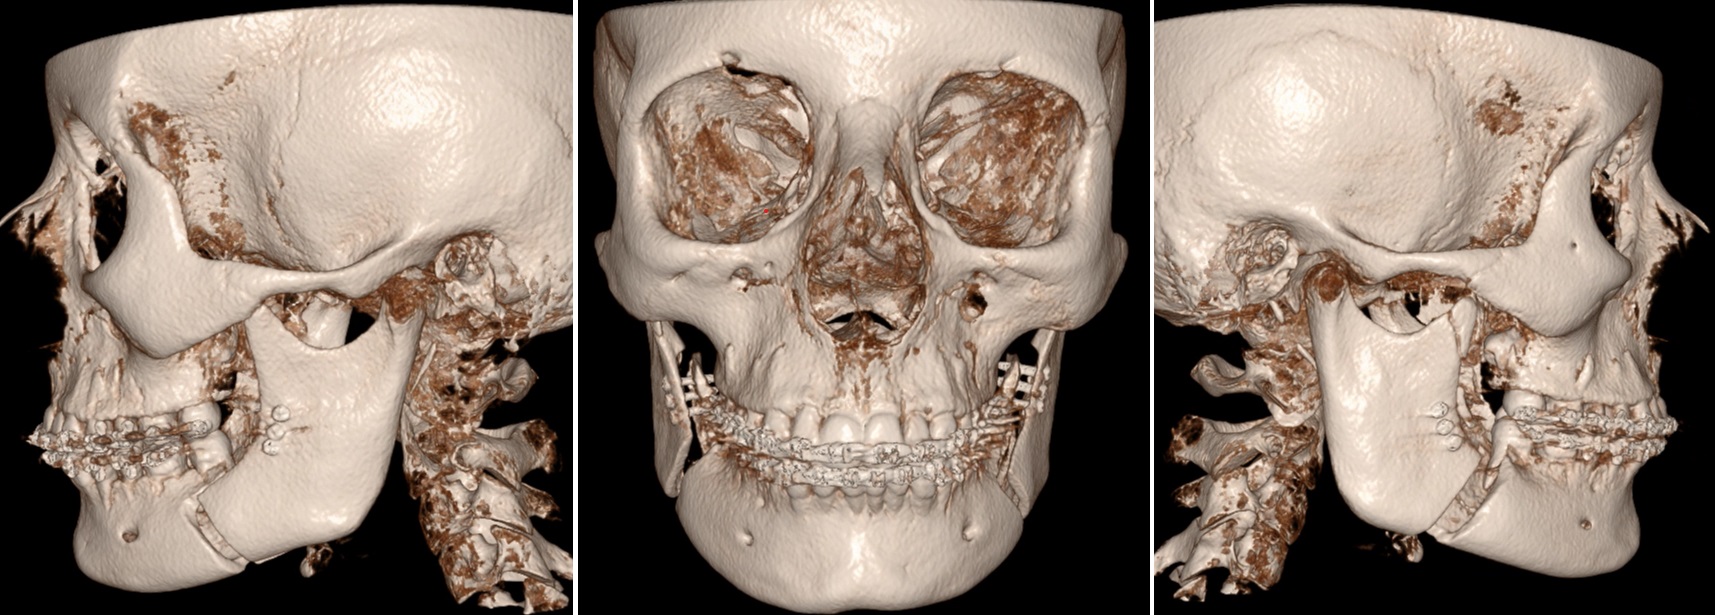

Vergrote overbeet door terugliggende onderkaak, onderkaak verlenging (BSSO advancement)

Röntgen beeld na operatie